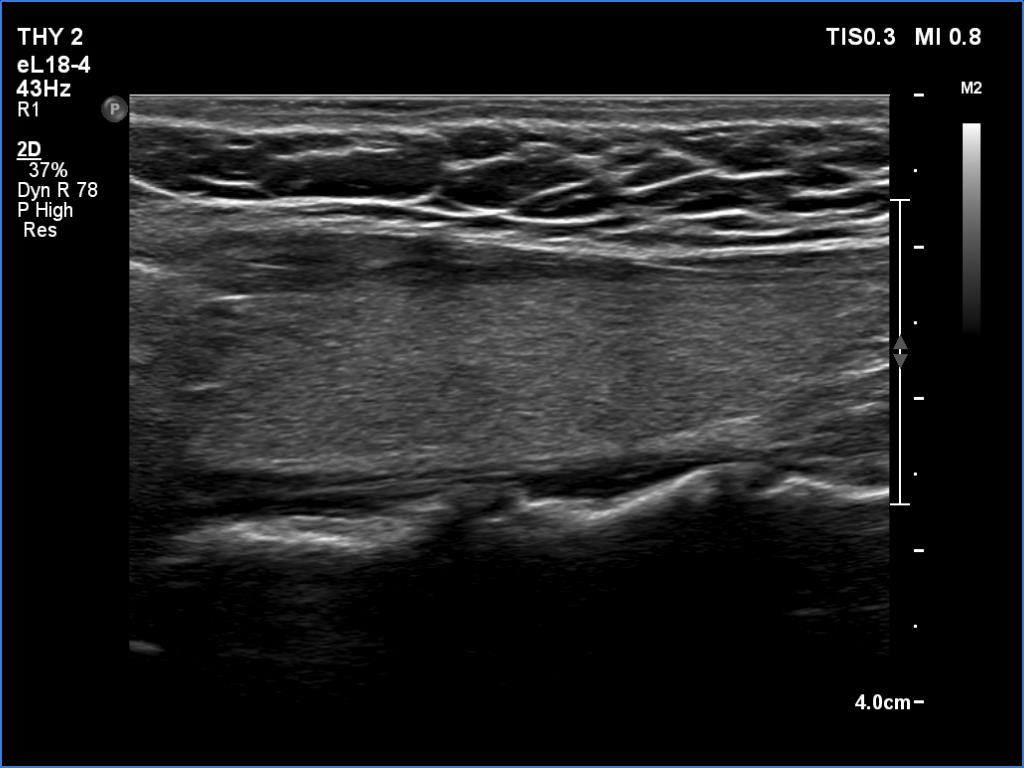

Introduction - case 487 (ultrasonographic picture 12)

Left lobe, longitudinal scan.